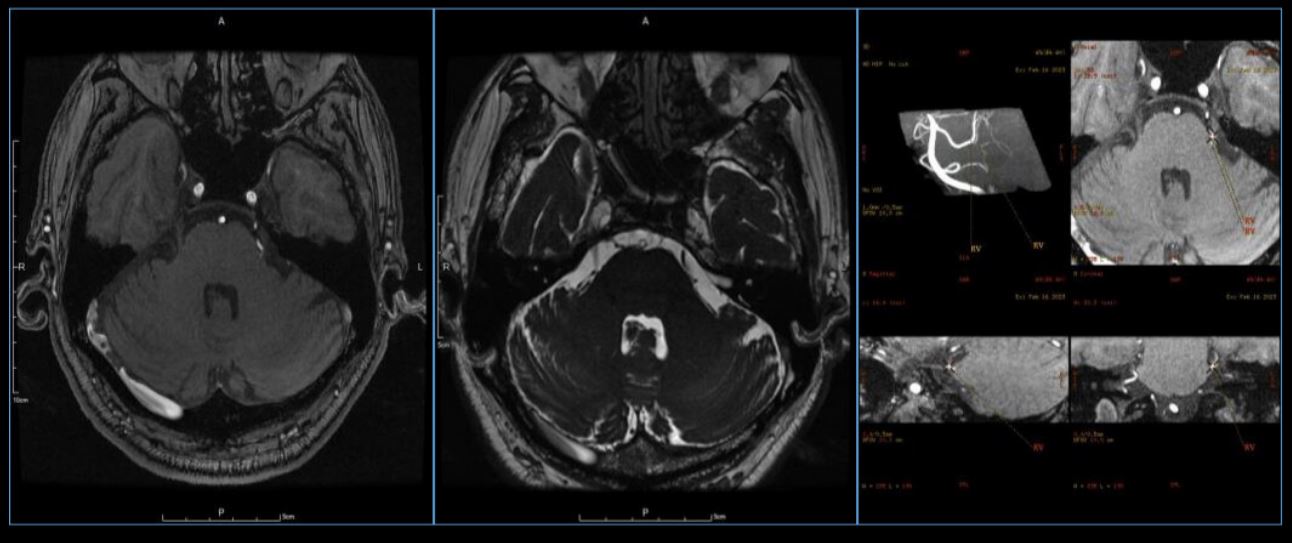

受此启发,我们近期完成1例内镜下经远外侧幕下小脑上入路三叉神经微血管减压术,目前国际国内未有相关文献报道,为该术式行内镜下MVD术国内外第一例,和大家一起分享。患者73岁男性,原发性三叉神经痛两年,口服卡马西平无效来我院治疗。术前磁共振提示左侧的小脑上动脉压迫三叉神经出脑干端(图1)。

图1